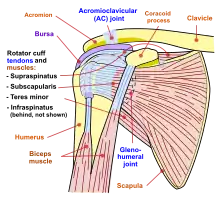

The shoulder joint is the main joint of the shoulder. It is a ball and socket joint that allows the arm to rotate in a circular fashion or to hinge out and up away from the body. The joint capsule is a soft tissue envelope that encircles the glenohumeral joint and attaches to the scapula, humerus, and head of the biceps. It is lined by a thin, smooth synovial membrane. The rotator cuff is a group of four muscles that surround the shoulder joint and contribute to the shoulder's stability. The muscles of the rotator cuff are supraspinatus, subscapularis, infraspinatus, and teres minor. The cuff adheres to the glenohumeral capsule and attaches to the humeral head.

Rotator cuff

The rotator cuff is an anatomical term given to the group of four muscles and their tendons that act to stabilize the shoulder.[3] These muscles are the supraspinatus, infraspinatus, teres minor and subscapularis and that hold the head of the humerus in the glenoid cavity during movement.[3] The cuff adheres to the glenohumeral capsule and attaches to the head of the humerus.[3] Together, these keep the humeral head in the glenoid cavity, preventing upward migration of the humeral head caused by the pull of the deltoid muscle at the beginning of arm elevation. The infraspinatus and the teres minor, along with the anterior fibers of the deltoid muscle, are responsible for external rotation of the arm.[6]

The four tendons of these muscles converge to form the rotator cuff tendon. This tendon, along with the articular capsule, the coracohumeral ligament, and the glenohumeral ligament complex, blend into a confluent sheet before insertion into the humeral tuberosities.[7] The infraspinatus and teres minor fuse near their musculotendinous junctions, while the supraspinatus and subscapularis tendons join as a sheath that surrounds the biceps tendon at the entrance of the bicipital groove.[7]